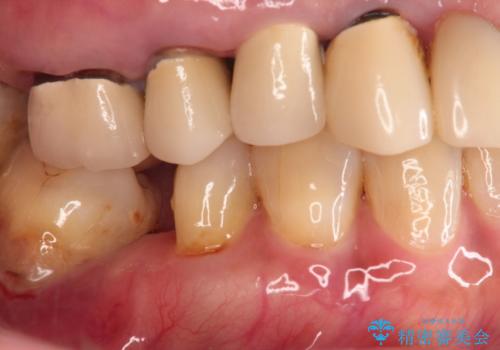

- 噛むと右の奥歯が痛い、何度も腫れを繰り返すとの事で来院された患者様です。

上顎は歯根破折と排膿が認められ、下顎も骨吸収により残せる状態ではないと判断し、抜歯後にインプラント治療(右上567、右下67)を行うことになりました。

上下のインプラント治療する事によりしっかり奥歯で咬めるようになり、患者様は大変喜ばれていました。